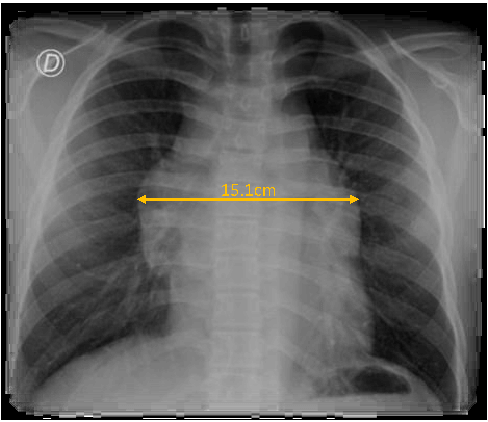

A 14-year-old boy, with a previous history of allergic rhinitis, presented to the PED due to sudden onset of a left cervical swelling. He had a six-month history of dry cough and for the last three days he had also been complaining of dyspnoea and thoracalgia (sudden onset during sleep), which was worsening and now radiating to the right shoulder. No other signs or symptoms. On examination, there was a mass on the anterior left cervical triangle, with approximately 2x3 cm, fixed to the muscle below, firm and non-tender. Laboratory studies revealed normal hemogram (hemoglobin 14.8 g/dL, leucocytes 9.3x1^3uL, neutrophils 68.2%, lymphocytes 21.6%) and elevated C-reactive protein (3.28 mg/dL, N<0.5 mg/dL) and lactate dehydrogenase (1113 U/L, N<230 U/L). The chest x-ray showed a large mediastinal mass (Figure 1) in the middle mediastinum, with a 15.13 cm width, prompting an urgent referral to Oncology. CT scan revealed several lymphoid masses, cervical bilateral (the largest on the left, 4x3 cm) (Figure 2) and at the anterior mediastinum (8.5x5.5cm, 7.5x4cm) (Figure 3). Abdominal CT was normal.

Figure 1. Chest x-ray: mediastinal mass (15.1 cm largest width).